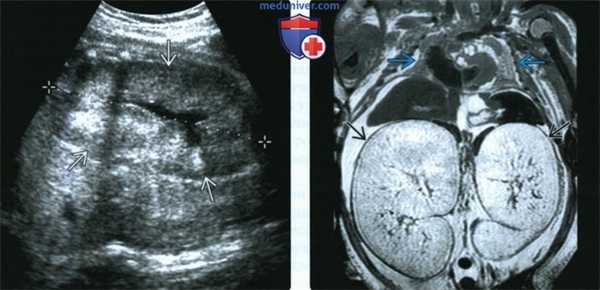

• Увеличенные почки дают однородный гиперинтенсивный сигнал в режиме Т2-ВИ

• Общий объем легких (ООЛ) позволяет прогнозировать исход:

о ООЛ: ГВ

(Слева) МРТ плода в 31 нед., фронтальная плоскость. Маловодие. Почки значительно увеличены, паренхима имеет нехарактерный гиперинтенсивный сигнал. Грудная клетка в форме колокола, уменьшена. Находки характерны для АРПКП с олигурией и, как следствие, гипоплазией легких.

(Справа) Аутопсия in situ. Почки значительно увеличены. Печень приподнята, обнажен подлежащий желчный пузырь. Почки занимают все пространство брюшной полости -от диафрагмы до малого таза.

(Справа) Посмертная МРТ, Т2-ВИ, фронтальная плоскость. Грудная клетка очень малых размеров. Почки значительно увеличены, нормальная паренхима отсутствует. Расширенные канальцы имеют гиперинтенсивный сигнал.